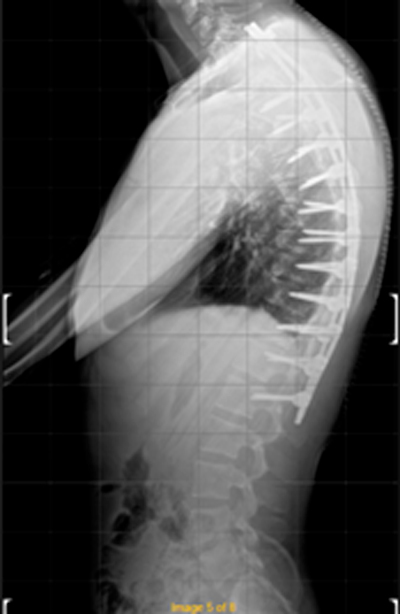

DIAGNOSI:

IPERCIFOSI DORSALE GRAVE

Radiografia dorsale pre operatoria

Intervento chirurgico eseguito:

STABILIZZAZIONE DORSO – LOMBARE CON OSTEOTOMIE CORRETTIVE

Radiografia dorsale post-operatoria